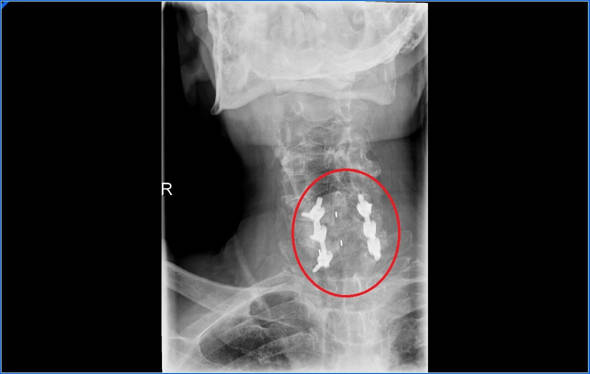

La técnica más utilizada es la artrodesis cervical, está técnica consiste en quitar las estructuras que están comprimiendo la médula. Normalmente el disco y estructuras óseas. Después de descomprimir la médula necesitaremos darle estabilidad al cuello por lo que tendremos que aportar injerto, placas y tornillos.

En determinados pacientes podremos poner una protesis discal, de este modo se mantiene la movilidad, normalmente se utiliza cuando no existe demasiada artrosis cervical.